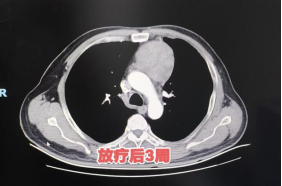

治疗全程患者无不良反应,与常规放疗相比,患者放疗疗程缩短一半,耐受性良好。放疗结束3周后复查显示,患者前纵隔占位显著减退,为后续治疗创造有利条件。

患者放疗前后肿瘤变化对比